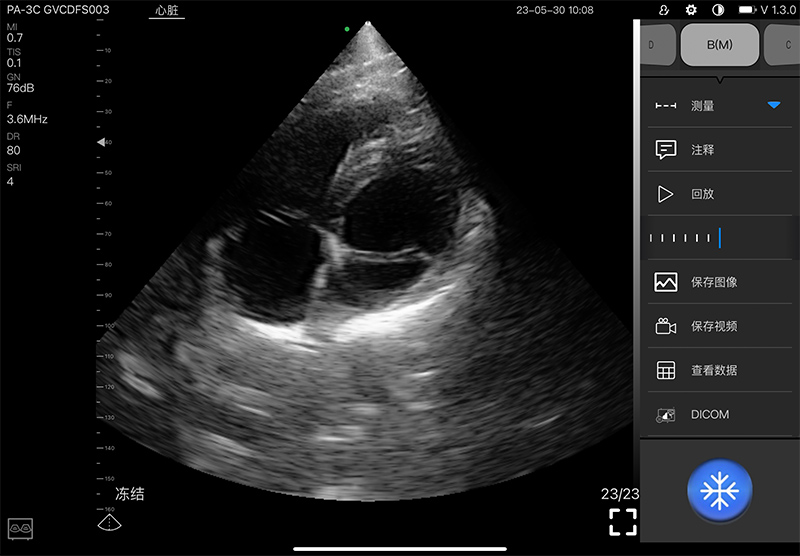

• 扫描方式: 电子相控阵扫描

• 阵元数:128

• 通道数:32

• 探头频率: 2.2-3.6MHz

• 增益30db-105db

• 扫描深度: 90/160/200/240mm,可调

• 扫描角度: 80°

• 显示模式: B、B/M、Color、PW、PDI

• 图像调节: 增益、焦点、反相脉冲谐波、降噪

• 图像帧频: 18f/s